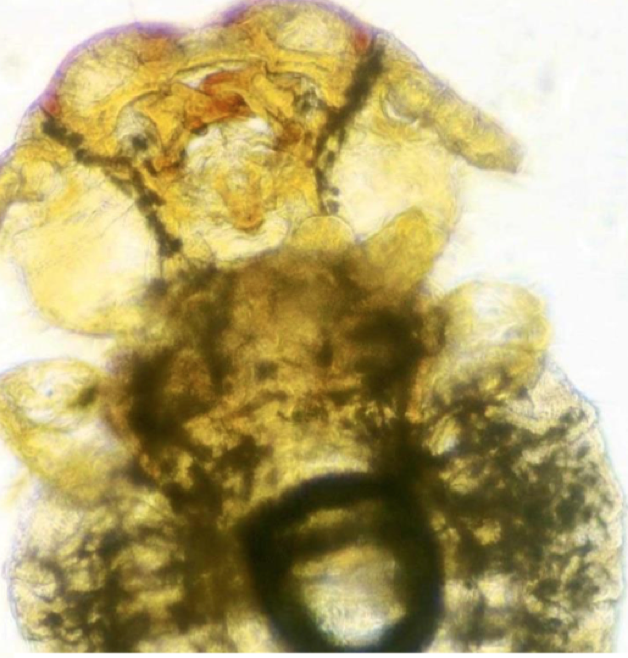

1

Q

identify this parasite

A

scabies (sarcoptes)